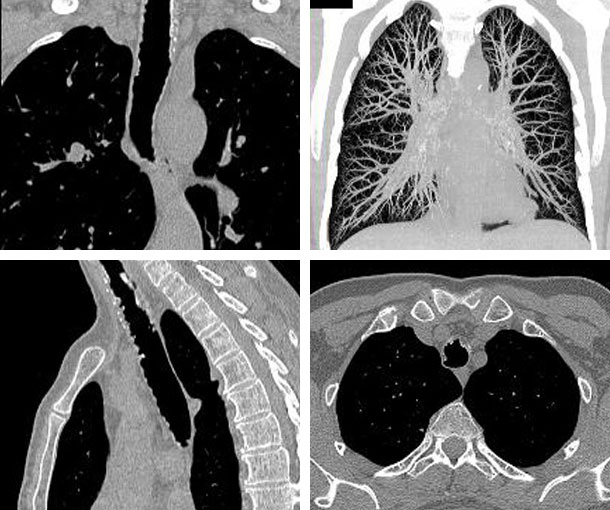

Tracheobronchopathia Osteochondroplastica (TO) CT Findings

- Nodules in the submucosa

- Typically 1-2mm in size

- Calcification is common

- Nodules arise from inner tracheal wall and into airway lumen

- Occurs in lower 2/3 of trachea and central bronchi

- Ossification

- Posterior membranous wall is usually unaffected